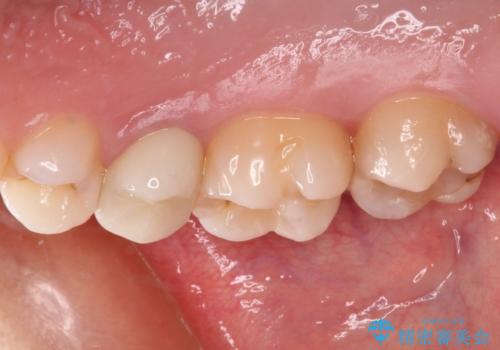

海外転居前にむし歯を治療したい 精密なむし歯治療

- 近々海外へ転居するとのことで、事前に処置をしておくべきむし歯がないか、気にして来院された患者様です。

レントゲン写真などから、速やかに処置を行うべき歯が2歯あったため、それぞれセラミックインレーとPGAインレー(ゴールドインレー)にて修復治療を行うこととしました。

どちらの歯も痛みなどの症状はなく、治療後も異常所見なく経過をたどっています。

上顎大臼歯は向かい合った人から見えることはほとんどないため、切削量が少なく、適合の良いゴールドインレーが大変おすすめとなります。